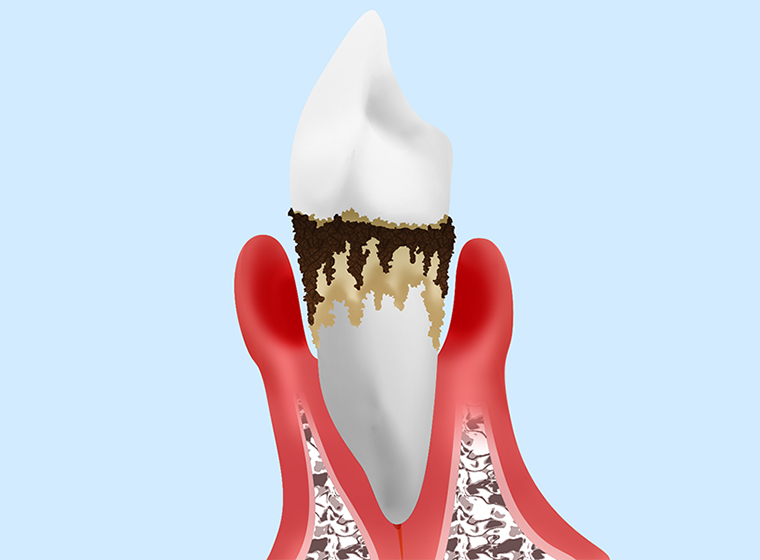

第3段階

|

歯周ポケットの深さが6mm以上と深くなり、さらに炎症が進んだ状態の「重度歯周炎」です。触れると痛みがあり、歯のぐらつきも大きくなり、放っておくと歯が抜け落ちてしまうこともあります。 |